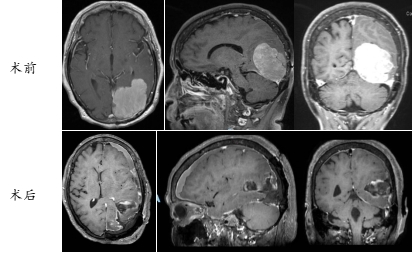

术前术后影像资料对比

· 术中“绣花”:在高清显微镜与实时神经电生理监测下,周东主任带领团队在神经与血管交织的精密网络中谨慎操作,成功将复发的脑膜瘤完整切除,完美保护了脑功能。

· 术后暖心康复:在多学科协作的精细化护理下,李奶奶恢复顺利,意识清晰,言语和肢体活动良好。家属的焦虑化为欣慰的笑容:“没想到母亲这个年纪,手术这么顺利,恢复得这么好!”